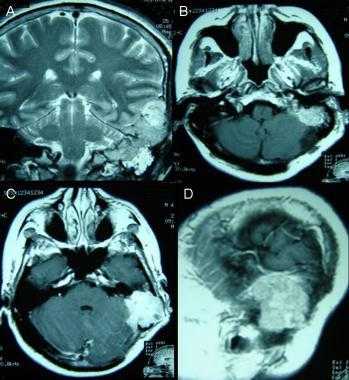

(Слева) Бесконтрастная КТ, аксиальный срез: определяется дольчатое гиперденсное объемное образование, расположенное по ходу намета мозжечка справа.

(Справа) МРТ, FLAIR, аксиальный срез: у этого же пациента визуализируется гипоинтенсивное многодольчатое объемное образование с перифокальным отеком и масс-эффектом на IV желудочек.

(Слева) МРТ, Т2-ВИ, корональный срез: у мужчины 47 лет определяется внемозговое образование однородной структуры с четкими контурами с минимальным отеком.

(Справа) МРТ, постконтрастное Т1 -ВИ, аксиальный срез: у этого же пациента визуализируется интенсивное относительно однородное контрастное усиление. Обратите внимание на компрессию треугольника левого бокового желудочка. Несмотря на отсутствие агрессивных рентгенологических признаков при хирургической резекции и гистологическом исследовании была диагностирована злокачественная Менингиома grade III. Для окончательного установления гистологического типа и степени злокачественности менингиомы необходима биопсия.

(Слева) МРТ, высокоразрешающее Т2-ВИ, аксиальный срез: у этого же пациента хорошо визуализируется гипоинтенсивное объемное образование с кистозными компонентами и четкими контурами. Гиподенсность указывает на высокое содержание клеточного матрикса в опухоли.

(Справа) МРТ, постконтрастное Т1-ВИ SPGR, корональный срез: контрастное усиление солидных компонентов опухоли. Было выполнено хирургическое удаление, был поставлен гистологический диагноз смеси светлоклеточного (grade II) и склерозирующего вариантов менингиомы.

(Слева) Злокачественная менингиома, инфильтрирующая кожу волосистой части головы, череп и смежные отделы головного мозга. Протяженной вазогенный отек изображен серым цветом. Обратите внимание на остеолизис, инвазию твердой/паутинной мозговой оболочки, «грибовидную» форму опухоли и ее «вплетение» в головной мозг.

(Справа) МРТ, постконтрастное Т1 -ВИ, сагиттальный срез: злокачественная менингиома, накапливающая контрастное вещество, и вовлекающая в процесс кожу головы, череп и смежные отделы головного мозга. Обратите внимание на «грибовидное» прорастание опухоли через твердую мозговую оболочку, выраженный гипоинтенсивный отек мозговой ткани. (Слева) МРТ, Т2-ВИ, аксиальный срез: у мужчины 71 года визуализируется объемное образование с четкими контурами, прилежащее широким основанием к твердой мозговой оболочке по ходу большого крыла клиновидной кости. Объемное образование изоинтенсивно по отношению к коре, отчетливо визуализируется ликворная щель, признаков локальной инвазии мозгвой ткани не отмечается.

(Справа) МРТ, постконтрастное Т1-ВИ, режим подавления сигнала от жира, аксиальный срез: интенсивное равномерное контрастное усиление. При операции признаков инвазии смежной мозговой паренхимы выявлено не было. При патоморфологическом исследовании была диагностирована менингиома grade II.